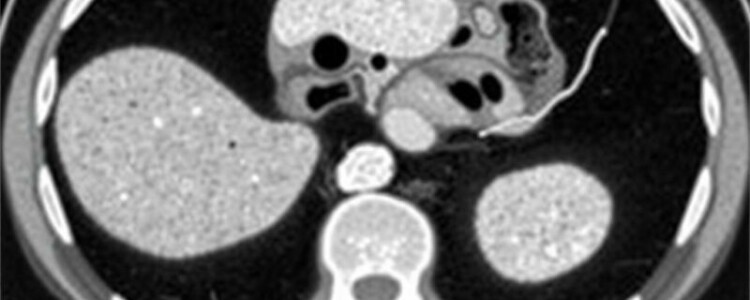

El signo más clásico es la dilatación del apéndice por encima de un diámetro umbral (frecuentemente >6 mm). Un apéndice no comprimible, de diámetro aumentado, con pared engrosada y pérdida de la transición mural es altamente suggestivo de apendicitis. El realce mucoso o mural tras contraste refuerza la sospecha. Otro hallazgo directo es la presencia de un fecalito intraluminal hiperdenso: su visualización dentro de un apéndice dilatado y con signos inflamatorios periféricos aumenta la probabilidad de apendicitis obstructiva.

Es importante recordar que el criterio numérico (por ejemplo, >6 mm) debe interpretarse en contexto: un apéndice distensible por gas puede ser mayor sin inflamación, y variaciones anatómicas pueden alterar la medida. Por eso la combinación de diámetro aumentado con signos inflamatorios periapendiculares logra la mejor precisión diagnóstica.

- Diámetro apendicular aumentado (>6 mm como referencia).

- Pared apendicular engrosada y realce con contraste.

Los signos indirectos son igualmente importantes: describen la respuesta del tejido periapendicular a la inflamación. La grasa periapendicular estriada es un hallazgo frecuente y con gran valor diagnóstico cuando aparece junto con un apéndice sospechoso. Es la representación tomográfica de la reacción inflamatoria de la grasa, y suele verse como líneas densas o cambios de atenuación en la grasa circundante.